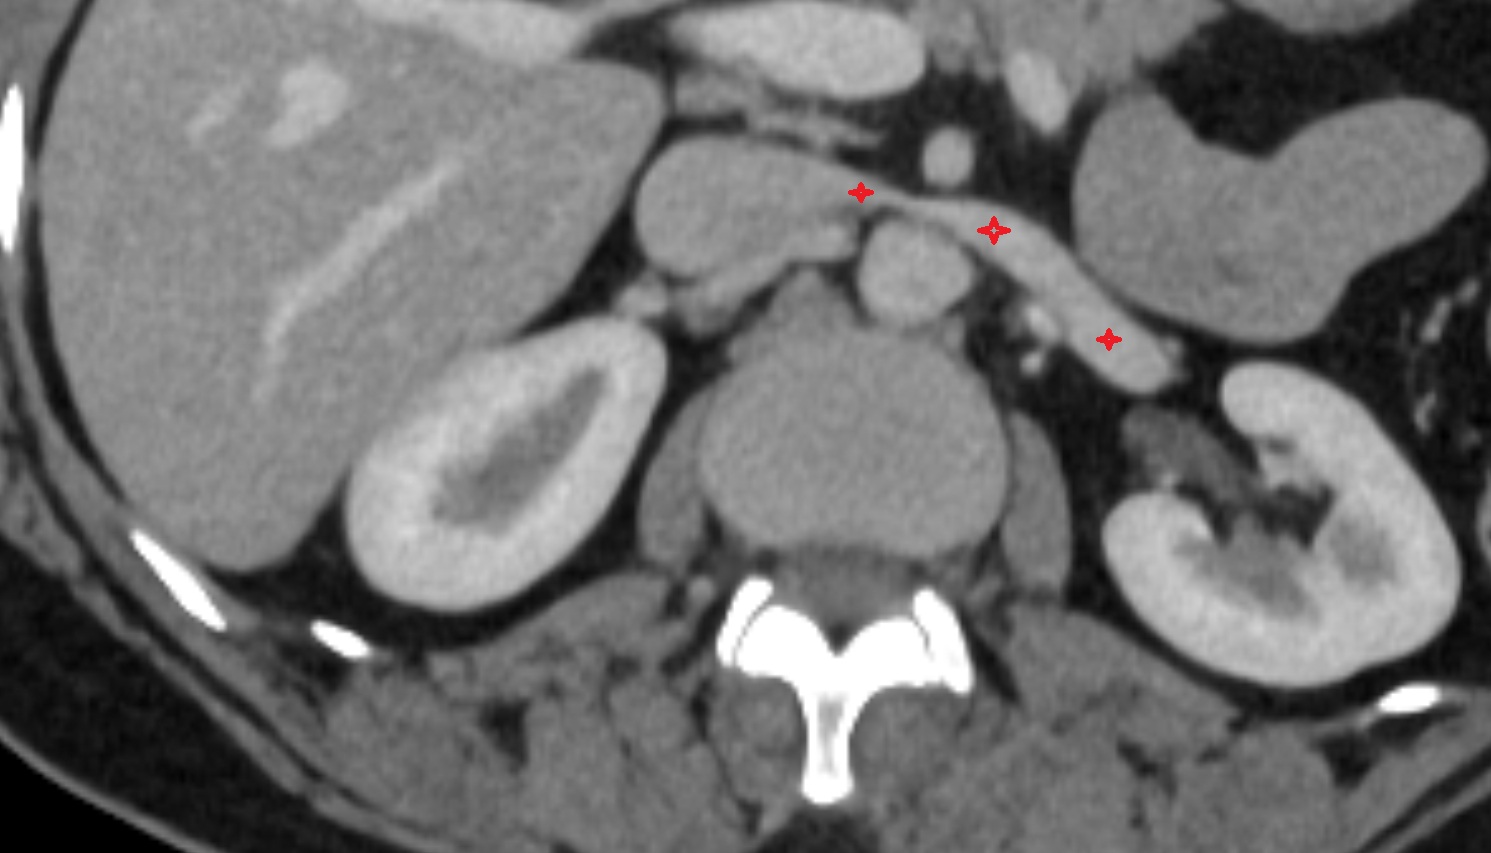

- kidneys

- Right kidney

- Left kidney

- Kidney cortex (Renal cortex)

- Renal capsule

- Renal medulla

- Renal pyramids

- Ureters

- Left ureter

- Right ureter

- Renal artery

- Renal vein

- Left renal vein

- Right renal vein

- Left renal artery

- Right renal artery